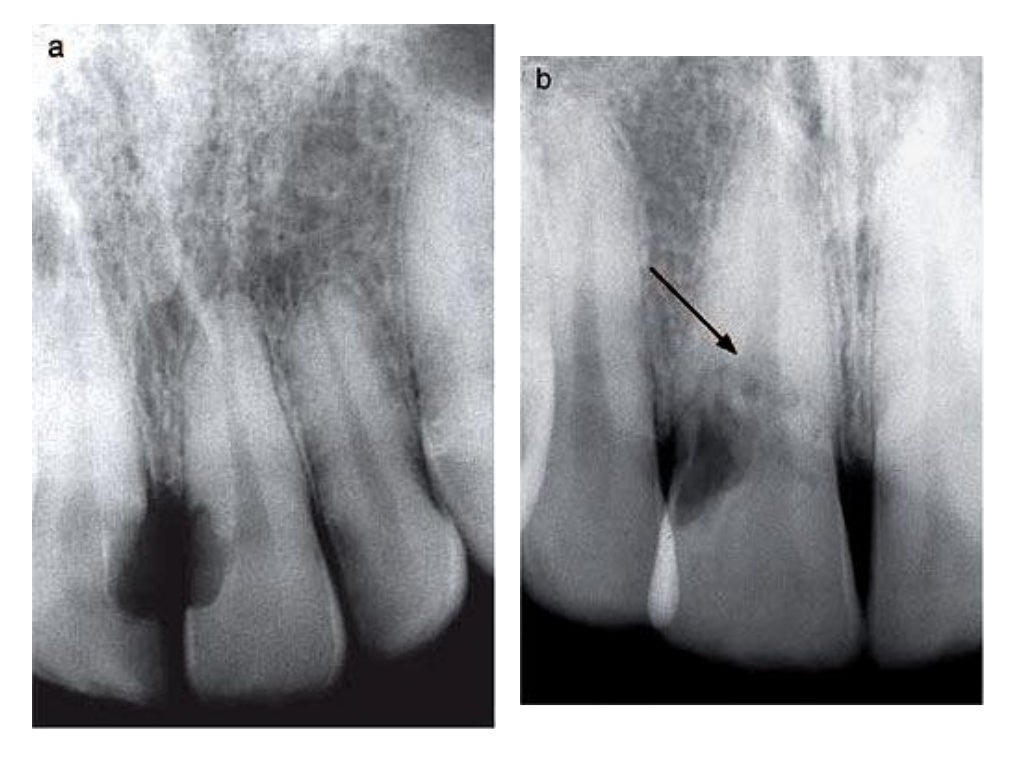

Radiological and Histopathological Features of Internal Tooth

Radiological and Histopathological Features of Internal Tooth What Is Dental Root Resorption tooth root resorption is multifactorial, leading to progressive destruction and eventual loss of tooth root dentin and cement. There are internal and external types of root resorption, each having its variety. tooth resorption, including root resorption, involves parts of the tooth being broken down by cells called osteoclasts. when a tooth undergoes root resorption, the body’s immune. What Is Dental Root Resorption.